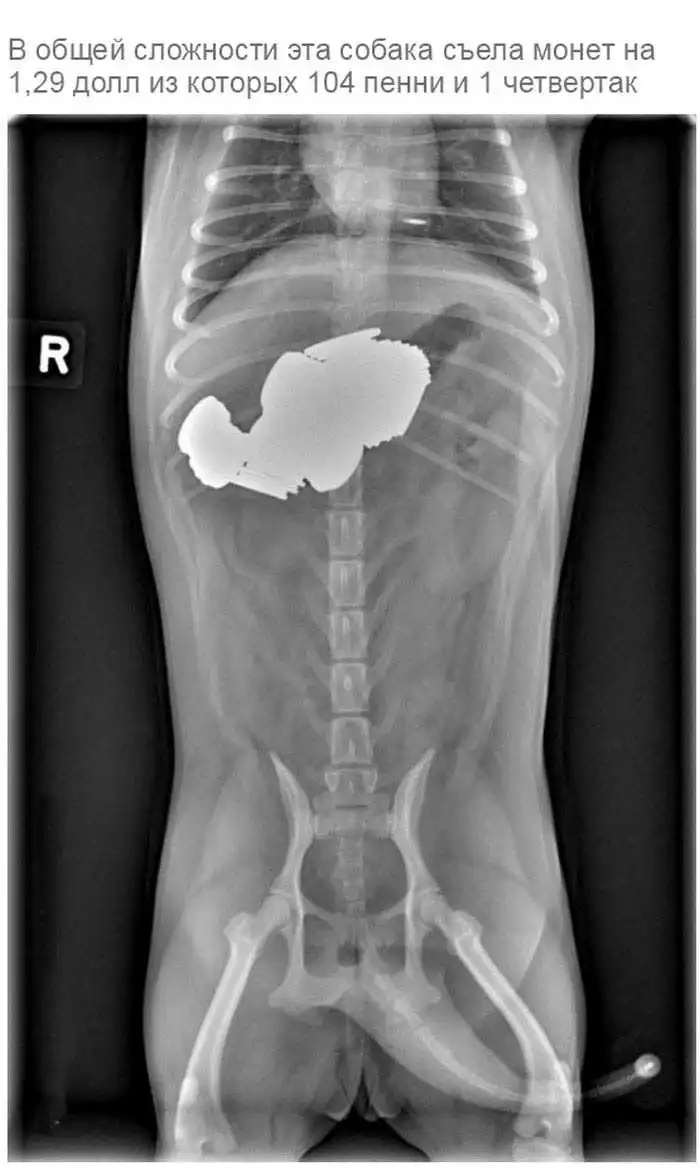

Что может оказаться в желудке собаки

Думаю, всем собачникам известно, что порой у собак бывают такие заскоки, когда они в прямом смысле слова жрут все подряд.